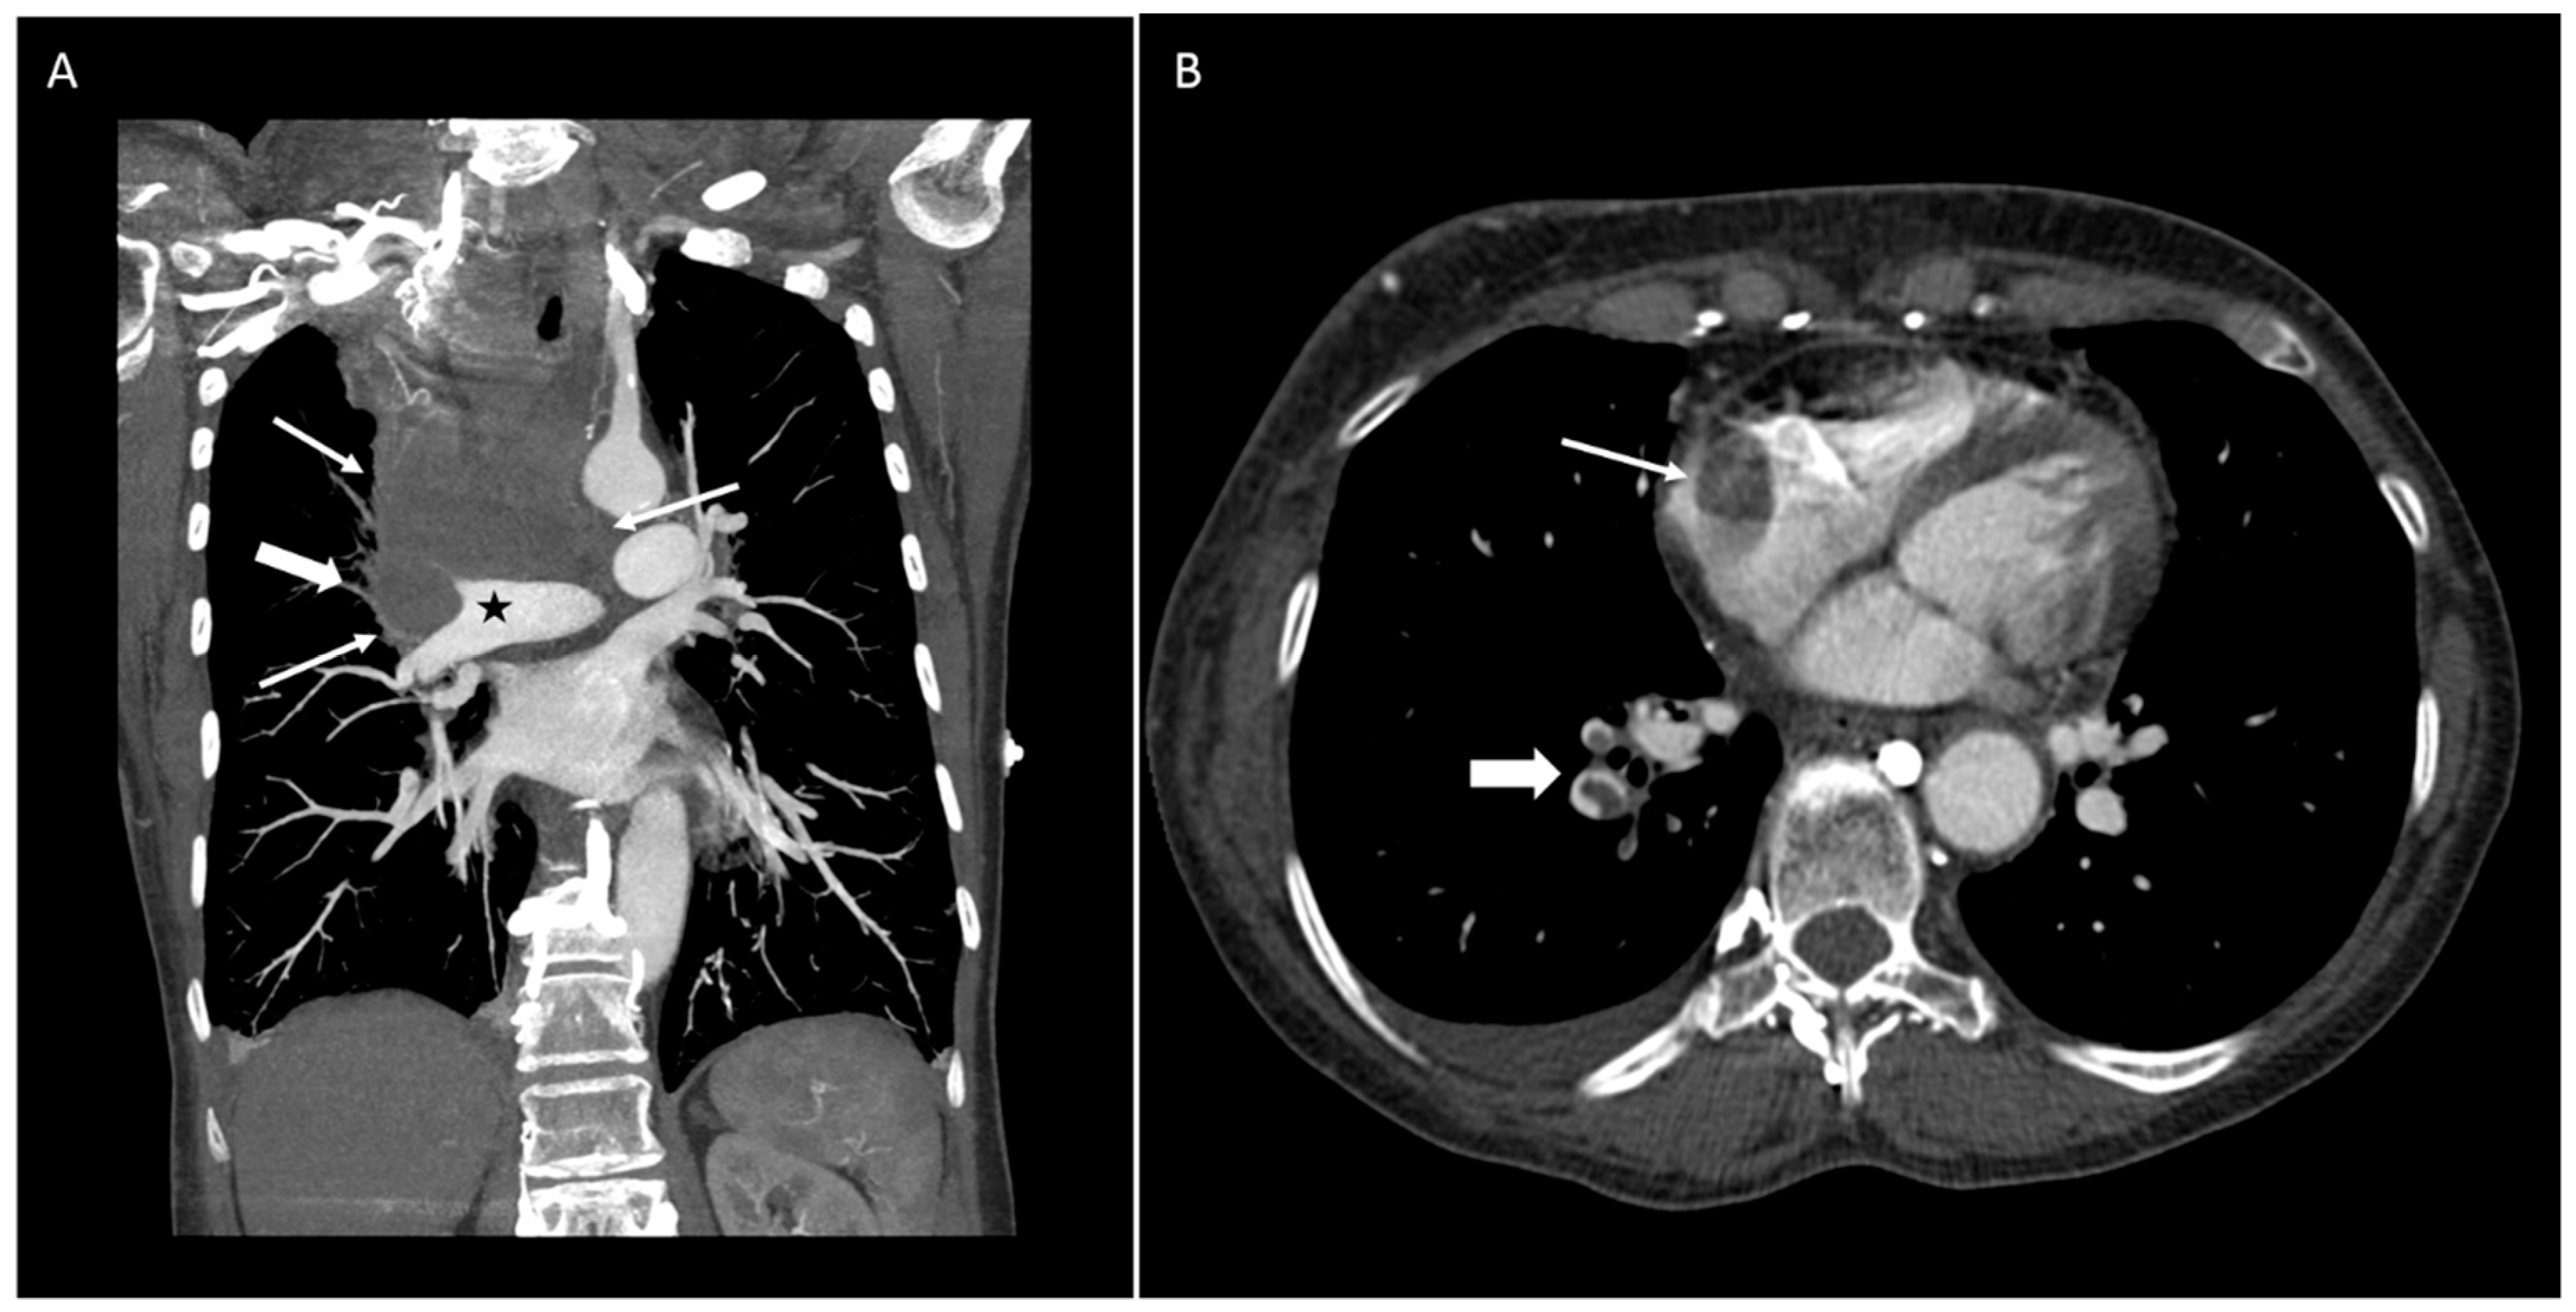

A 64-year-old woman with a past medical history of Grave’s disease presented to the hospital complaining of sudden onset of facial and bilateral arm swelling, as well as "bruising" in her neck, abdomen, and arms, all of which she developed over a few days. Further, the patient reported fatigue, neck tightness, and dyspnea on exertion. She denied any other symptoms and the remainder of the full review of systems, including weight loss, was negative. Social history was significant for 40 years of smoking. The patient was hemodynamically stable with good oxygenation on 2 L of oxygen by nasal cannula. Physical exam revealed swelling of the face, neck, and both arms, superficial varicosities on the neck, chest, back, and arms, as well as mild inspiratory stridor. Computed tomography angiography (CTA) of the thorax and neck showed a large central mediastinal mass occluding the pulmonary artery and extending into the right atrium, encasing the superior vena cava (SVC), abutting the trachea but not causing tracheal narrowing (Figure 1A), as well as pulmonary emboli at the right lower lobe (Figure 1B). Given the tobacco abuse history, lung cancer leading to SVC syndrome was suspected, although other malignancies such as lymphoma were in the differential. The patient was started on a heparin drip and the Pulmonary and Hematology-Oncology services were consulted, both of which agreed for the need for tissue diagnosis of the likely malignancy and rapid initiation of treatment.

Figure 1.

CT image of the thorax from outside the hospital showing (A) a large central mediastinal mass, occluding the pulmonary artery and extending into the right atrium, encasing the superior vena cava (SVC), abutting the trachea; and (B) pulmonary emboli at the right lower lobe.